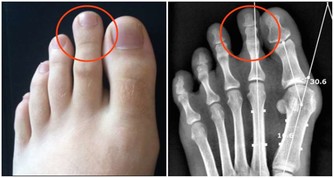

功效:淤積濕寒的風濕性關節炎

1、干紅辣椒25 個,花椒30 克。

2、花椒加水3000 毫升,文火煎半小時,放入紅辣椒煮軟取出,去籽。

3、將辣椒皮撕開,貼於患處,共貼三層(可用紗布綁住),敷10 分鐘左右(可根據自己的忍耐程度縮短敷治的時間)。

4、每晚敷1 次,連敷1 週。

注:連續用的花椒水中,放入的辣椒皮必須每次更新。